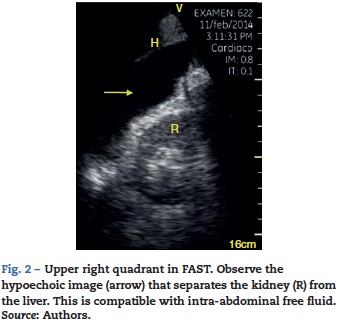

FAST consists of the evaluation of four points (pericardial, perihepatic, perisplenic, and pelvic (Fig. 1)) to detect hypoechoic images related to free pericardial and intra-abdominal fluids of up to 100 ml (Fig. 2) with a sensitivity of 50-88%. Its application has managed to reduce mortality from cardiac and abdominal trauma.17 Its extended application to the thorax (EFAST) for detecting pneumothorax and hemothorax has been very important.18 Firstly this is because it is more sensitive than radiography techniques for diagnosing pneumothorax (48% vs. 20%),17 a pathology that is calculated to be hidden in 5% of all traumas19 and in up to 55% of severe traumas.20 Secondly, echography may detect fluid with a volume of 20 ml while radiography detects 200 ml.21 Thus, echography has a superior sensitivity and specificity when it comes to detecting hemothorax.22

Pleural effusion should be searched for in the perisplenic and perihepatic quadrants of EFAST, moving two intercostal spaces in the direction of the head to locate the diaphragm.24 Normally, in the direction of the head from the diaphragmatic cupola there is a reflection of the spleen or the liver (Fig. 1C) while, in the presence of pleural effusion, a hypoechoic image can be observed and the lung compresses giving it the appearance of a solid organ (hepatization) (Fig. 16).24